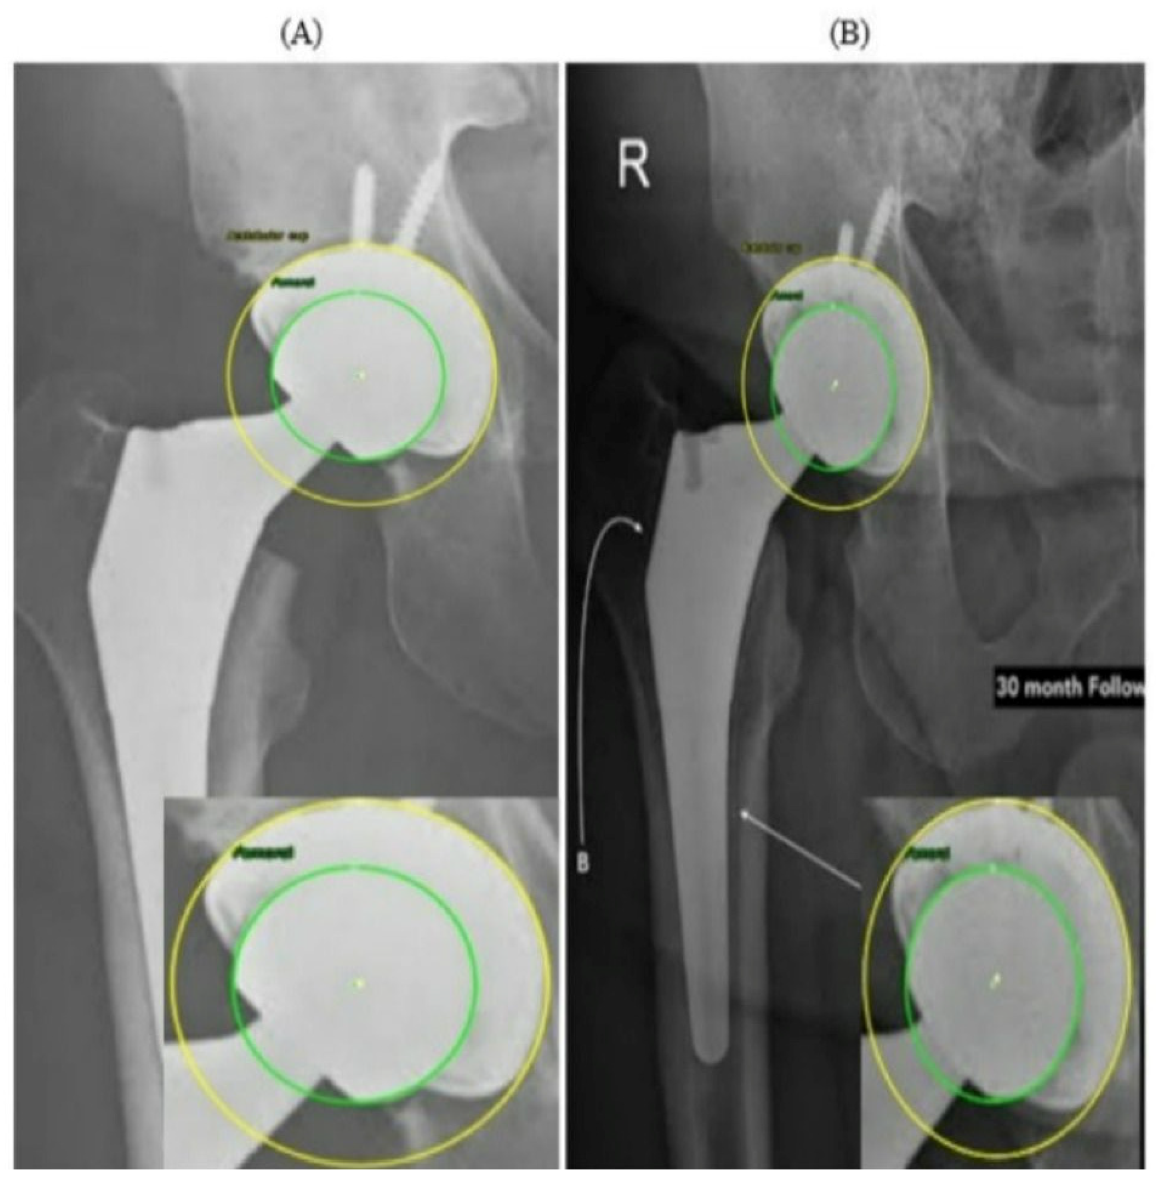

Figure 11 presents two radiographs from the same patient acquired at different time points. In the PRE image (Figure 11A), the prosthetic components appear well aligned, with symmetric and uniform joint spaces surrounding the femoral head. No displacement or asymmetry is observed, and the head is centrally positioned within the AC. In contrast, the 30-month POST radiograph (Figure 11B) shows a subtle superior migration of the femoral head. This displacement produces a clear difference in the superior joint space, together with a relative widening of the inferior gap, indicating superior polyethylene wear. A mild medial shift of the femoral head center is also visible, reflected by narrowing of the joint space on the medial side and confirming the occurrence of medial wear. Thus, the joint space that was initially symmetrical has become asymmetrical over time due to combined superior and medial displacement. This pair of radiographs clearly illustrates the progression of wear over the 30-month period, demonstrating a consistent superomedial direction of femoral head penetration within the AC. Both radiographs in Figure 11 originate from the external evaluation dataset and were not included in the training process.

Figure 11.

Example 1 of PRE–POST radiographs with detected femoral head and AC circles. (A) PRE radiograph demonstrating a centered femoral head within the acetabular cup. (B) POST radiograph showing superior displacement of the femoral head consistent with wear progression.

These findings reinforce the value of combining visual and quantitative evidence when interpreting longitudinal THA radiographs. While subtle migration patterns can be difficult to identify through visual inspection alone, particularly when the displacements are only a few pixels, the automated circle-based analysis provides a reproducible framework for detecting even minimal deviations from baseline alignment. The PRE–POST differences captured in Figure 11 and Figure 12 demonstrate how small variations in center position and joint-space geometry accumulate over time to form clinically meaningful wear trajectories. Importantly, the refined circle estimates reduce the influence of image noise, projection variability, and partial rim visibility, ensuring that the observed displacements reflect true anatomical change rather than measurement artifacts. By integrating both geometric overlays and numerical wear metrics, the system enables a clear linkage between qualitative radiographic appearance and quantitative displacement values. This dual-layer interpretation helps distinguish early progressive wear from normal postoperative variation and supports more consistent longitudinal monitoring of implant performance.

Two representative wear cases were quantitatively summarized in Table 3 and Table 4, each including a pair of PRE and POST radiographs along with the automatically computed medial, superior, and resultant wear components. In both examples, the system successfully produced consistent numerical outputs after scale normalization. These examples demonstrate the ability of the proposed framework to extract reliable and fully automated wear measurements. When a magnification factor is available, pixel-based wear values can be converted to millimeters using the following:

Table 3.

Automatic measurements and calculated wear values for Figure 11.